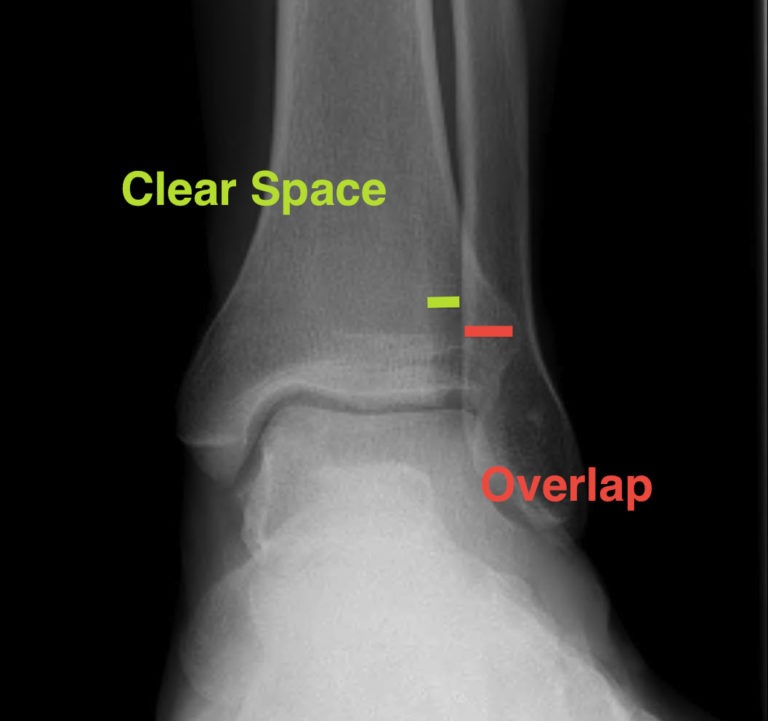

Normal values at standard Xray views (AP,Mortise and lateral)of the Ankle X Ray Labeled The series is often used in emergency departments to evaluate the distal tibia,. This projection is used to assess the distal tibia and fibula , talus , navicular , cuboid , the base of. Ankle radiographs are frequently performed in emergency departments, usually after trauma. Occasionally the articular surface of the talus can be injured. The ankle is the most. Ankle X Ray Labeled.